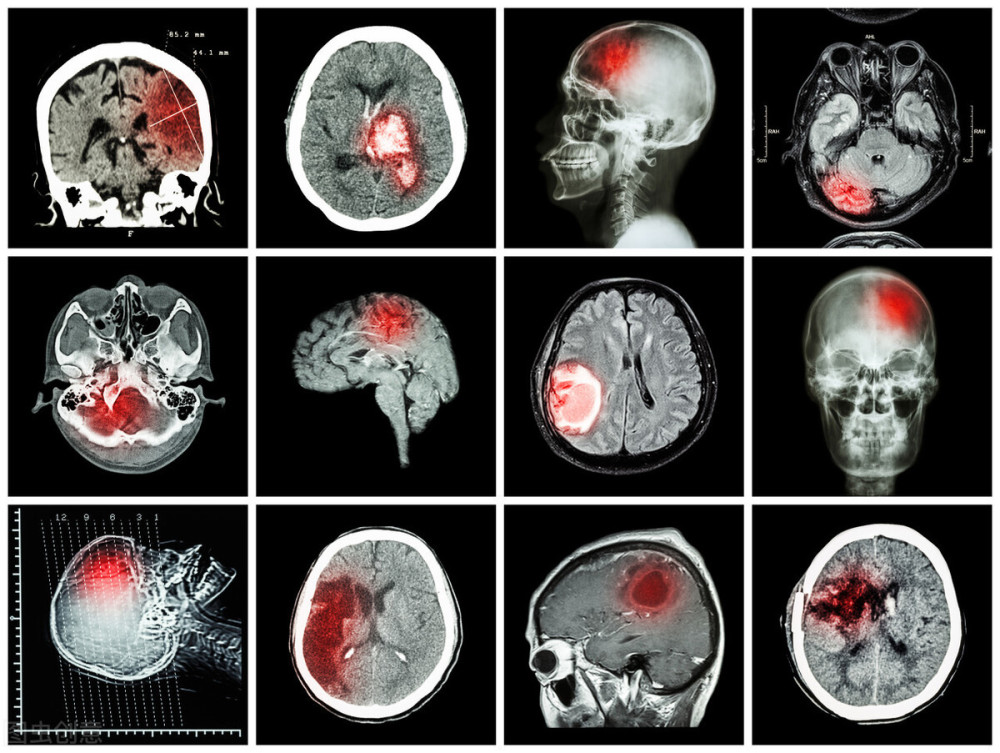

文章插图